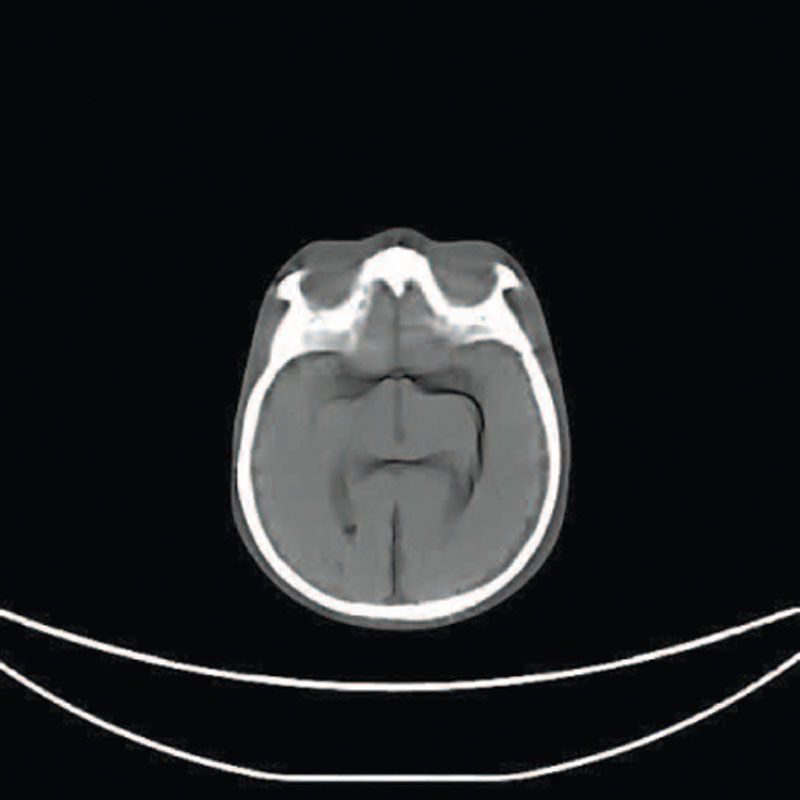

Ein einzigartiges Ganzkörperphantom für CT bietet eine Vielzahl von Ausbildungs- und Forschungsmöglichkeiten. Das Phantom kann auch für normales Röntgen benutzt werden und gibt lebensnahe Bilder. Es benden sich keine Metallteile oder Flüssigkeiten im Phantom. Die wichtigen Gelenke haben eine menschenähnliche Beweglichkeit und erlauben vielfältige Positionen für die Übung. Das Phantom kann in 10 Teile zerlegt werden. Die verbesserten Schultergelenke erlauben es, die Arme nach oben zu bewegen. Die künstlichen Organe sind anatomisch korrekt und haben entsprechende HU-Zahlen.

- Gehirn

Radiologische Absorption und Hounsfield-Nummer ähnlich dem menschlichen Körper.